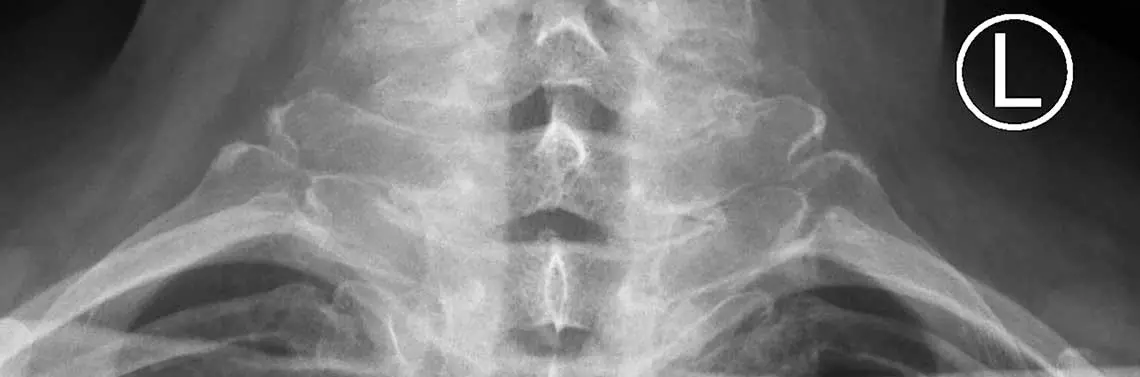

Zesztywniające zapalenie stawów kręgosłupa (ZZSK, choroba Bechterewa) jest przewlekłą, autoimmunologiczną, seronegatywną chorobą z grupy spondyloartropatii. Najczęściej zajmuje szkielet osiowy oraz stawy krzyżowo-biodrowe, których dolegliwości bólowe są zwykle początkowymi objawami. W przebiegu schorzenia zmiany postępują z czasem, często z okresami remisji. ZZSK stopniowo obejmuje wszystkie części kręgosłupa, co skutkuje jego zupełnym zesztywnieniem. Skostnieniu ulegają więzadła oraz stawy między wyrostkami poprzecznymi kręgów. Zmianami chorobowymi mogą być zajęte również inne stawy (najczęściej stawy biodrowe), przyczepy ścięgien (entezopatie) oraz gałki oczne (zapalenie błony naczyniowej oka).